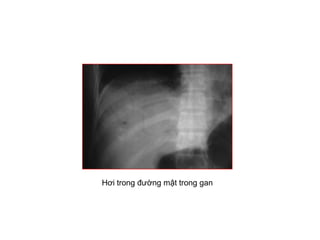

• Hôi trong tónh maïch cöûa, ñöôøng maät

Hơi trong đường mật trong gan